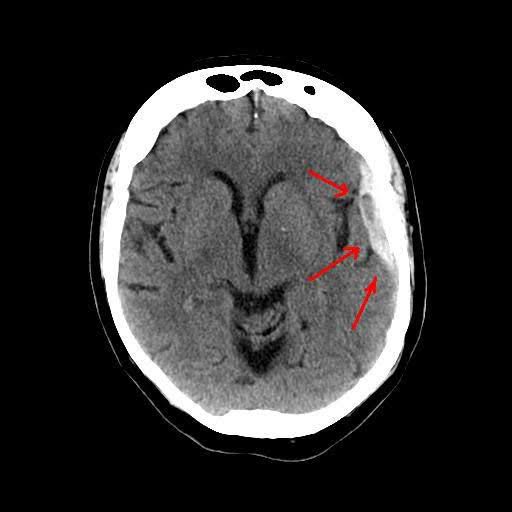

Cause of subdural hemtoma

The most common cause for a subdural hematoma is head injury. This can be from a car crash, fall, or violent attack. This sudden impact can strain the blood vessels within the dura, causing them to rip and bleed.